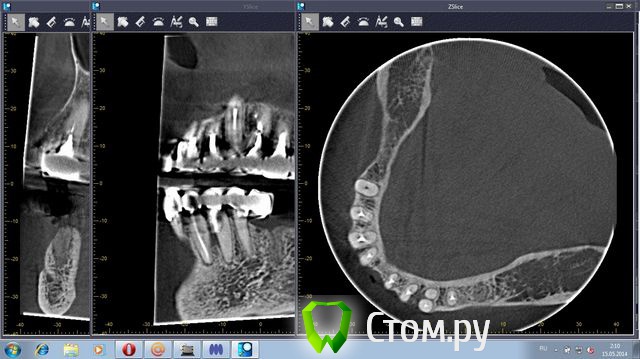

stradalitca Опубликовано 20 мая, 2014 Автор Поделиться Опубликовано 20 мая, 2014 (изменено) Добрый вечер! Я тут ещё глянула как установлен штифт на четвёрке снизу справа. Вот фото в проекциях. Неужели зуб тоже пробит штифтом? или пойдёт ? и я зря переживаю. Изменено 20 мая, 2014 пользователем stradalitca Ссылка на комментарий

Korel Опубликовано 23 мая, 2014 Поделиться Опубликовано 23 мая, 2014 Неужели зуб тоже пробит штифтом? Похоже на то. А Вы не рассматривали для Вашей мамы вариант (на н\чел.) бюгельный протез с замковыми креплениями. 1 Ссылка на комментарий

stradalitca Опубликовано 23 мая, 2014 Автор Поделиться Опубликовано 23 мая, 2014 почитала про мплантанты. Получается, что нам это не особо подходит. Начиная с того, что надо вылечить всю остальную челюсть - то есть убрать очаги воспаления. А воспаление видно невоооружённым глазом. Сегодня у неё стала кровить нижняя четвёрка справа. то ли от полосканий солью, то ли дают знать о себе очередной неудавшийся штифт.А бюгельный протез Вы предлагаете на место моста из 9 коронок и плюс 5,6,7 слева? я правильно поняла? Ссылка на комментарий